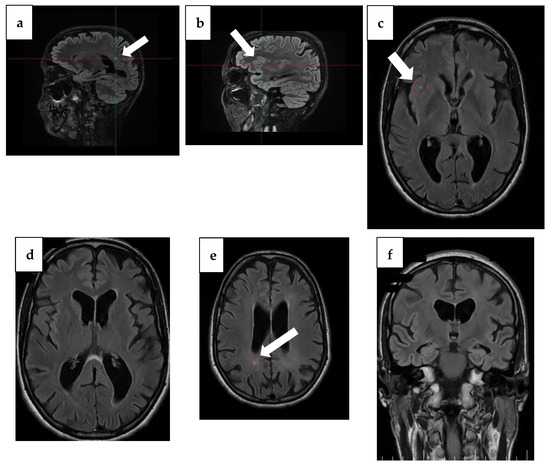

| Baseline (4 years ago) | MMSE 16/30 | Tau, p-Tau, Aβ42 within normal limits; 14-3-3 negative | Temporal atrophy; two punctiform FLAIR lesions (insula + occipital horn); ex vacuo ventriculomegaly | Initial cognitive decline after vestibular neuritis; onset of disorientation and working memory/language deficits |

| Year 3 (1 year ago) | MMSE 9/30, MoCA 4/30 | Tau ↑ 877 pg/mL; p-Tau ↑ 63.6 pg/mL; Aβ42 ↓ 0.94 | Hippocampal atrophy (MTA score 2); parietal atrophy (Koedam 2); severe corpus callosum thinning with splenium demyelination (T2/FLAIR hyperintensity, T1 hypointensity) | Severe cognitive disorder requiring permanent care; anxiety and depression prominent |